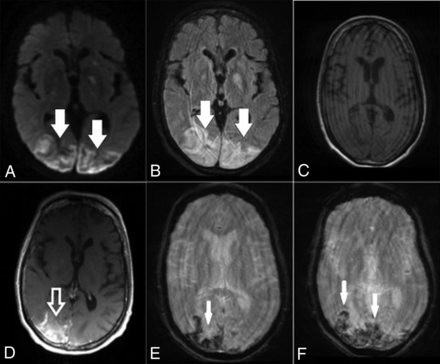

He subsequently developed fever and cough on March 17, had polymerase chain reaction testing positive for SARS-CoV-2, and was admitted into a local hospital for medical care. Two days later, the fever progressed to 105°F and he developed difficulty breathing and was transferred to a tertiary medical center for intensive care unit care and was placed on mechanical ventilation. On March 25, he developed shock with widely varying blood pressures from 70/30 to 180/90 mm Hg during his intensive care stay. On April 4, he was diagnosed with inflammatory cytokine release syndrome (high D-dimer, lactate dehydrogenase, C-reactive protein, and ferritin values) and developed an altered mental status. Noncontrast CT of the head was obtained and demonstrated focal vasogenic/cytotoxic edema in the posterior parieto-occipital regions bilaterally, which was subcortical in distribution, with a small right-sided hemorrhage (Fig 1); concurrently obtained CT venogram findings were normal. The patient was extubated and transferred to a medical floor on April 10, with gradual improvement in his mental status. MR imaging of the brain was performed on April 13 and confirmed vasogenic edema in the posterior parieto-occipital regions with subacute blood products suggestive of hemorrhagic posterior reversible encephalopathy syndrome (PRES). SWI revealed extensive petechial hemorrhages diffusely distributed throughout the corpus callosum (Fig 2).

Brain axial DWI (A), FLAIR (B), precontrast T1-weighted (C), postcontrast T1-weighted (D), and susceptibility-weighted (E and F) images obtained 8 days after CT demonstrate a small infarct in the right occipital region (arrow, A), persistent edema in the posterior parieto-occipital regions (hollow black arrows, B), subacute blood products in the location of the infarction (solid white arrow, C), and some contrast enhancement (hollow white arrow, D). There are diffuse petechial hemorrhages on SWI throughout the corpus callosum (white arrows, E and F).

On March 25, she developed altered mental status, including lethargy and confusion, and was transferred to our hospital. In the emergency department, the patient was afebrile, with laboratory values notable for Cr = 1.65, blood urea nitrogen = 23, lactate = 2.3, and mild hyponatremia. Arterial blood gases were normal, and she denied cough, chest pain, and shortness of breath. The patient had variations in blood pressure, ranging from 115/72 to 178/83 mm Hg at admission. Chest CT demonstrated bilateral multifocal ground-glass opacities concerning for COVID-19 pneumonia due to its high prevalence in the region. Findings of a polymerase chain reaction test were positive for SARS-CoV-2 on March 27. Noncontrast head CT demonstrated edema in the bilateral parieto-occipital regions with associated mass effect and cortical sulcal effacement (Fig 3). MR imaging of the brain performed on March 27 revealed multiple areas of restricted diffusion with associated edema, most extensive in the posterior parieto-occipital lobes but also in the right frontal lobe, basal ganglia, and cerebellar hemispheres. The SWI sequence demonstrated extensive superimposed hemorrhages in the parieto-occipital region along with abnormal enhancement (Fig 4). Findings of concurrently performed MR angiography of the head and neck were unremarkable: Specifically, evaluation of the posterior circulation demonstrated a patent vertebrobasilar system. The patient remained afebrile with normal respiratory status, including oxygen saturation; after gradual improvement in her mental status, she was discharged.

Brain axial DWI (A), FLAIR (B), precontrast T1-weighted (C), postcontrast T1-weighted (D) and SWI (E and F) obtained after CT demonstrate bilateral posterior infarctions (white arrows, A), edema in the posterior parieto-occipital regions (white arrows, B), and some contrast enhancement (hollow white arrow, D; compare with C). Selected SWI shows extensive blooming artifacts compatible with hemorrhages predominantly in the cortex (white arrows, E and F). Findings are more pronounced on the right side.